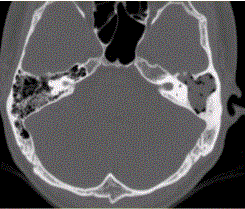

问题 患者男,25岁,右耳流脓液、听力下降5年。查体:右侧鼓膜穿孔,传导性耳聋,CT检查如下图。 胆脂瘤型中耳乳突炎多发于

选项 A.气化型乳突 B.囊肿型乳突 C.硬化型乳突 D.板障型乳突 E.混合型乳突 F.液化型乳突

答案 CD

解析 CD